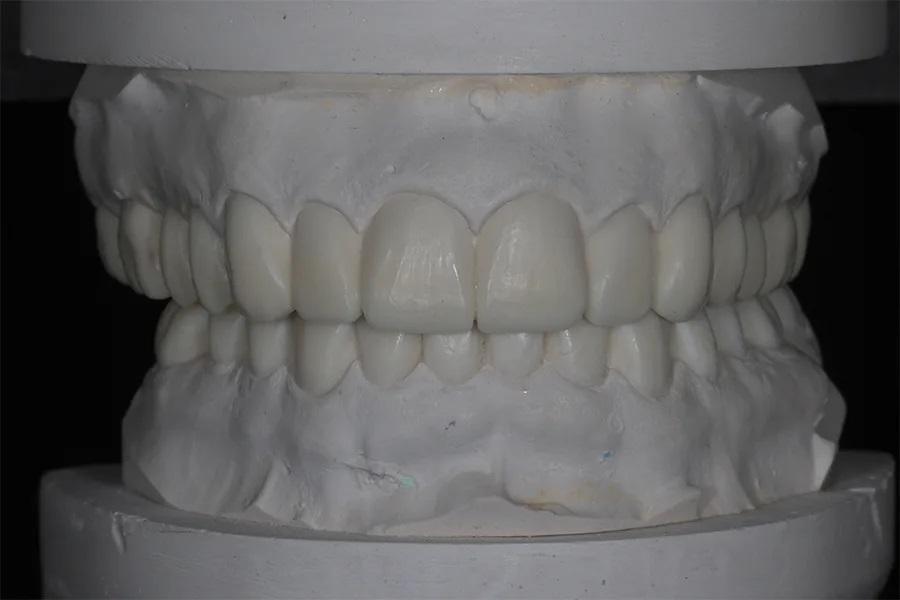

Зуботехнической лаборатории было дано указание увеличить длину верхних клыков на 2 мм, чтобы обеспечить положение клыков на уровне 0 мм в покое. Также лаборатории было поручено выровнять остальные зубы верхней зубной дуги относительно платформы. В нижней зубной дуге планировалось восстановление длины передних зубов и анатомии боковых зубов. Через 4 месяца имплантат в области зуба 15 интегрировался, и работа была направлена в лабораторию для выполнения воскового моделирования с увеличенным ВРО (фото 8).

Фото 8. Полное восковое моделирование в артикуляторе.